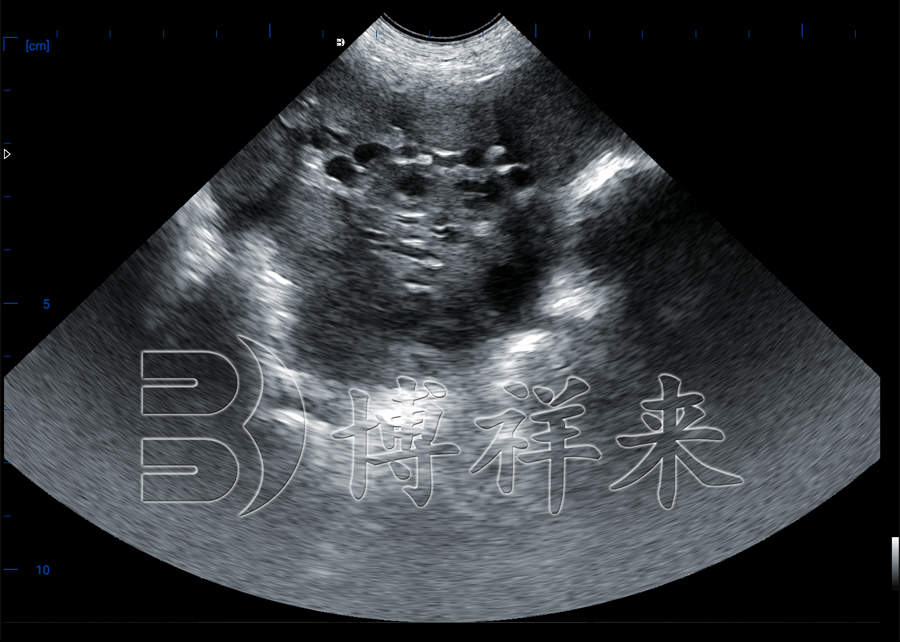

猪用卵泡检测B超机,是一种利用超声波技术检测母猪卵巢内卵泡发育情况的兽用设备。与传统的妊娠检测不同,它的重点在于检测卵泡的数量、大小、位置和是否成熟,为人工授精提供最精准的时间窗口。

该设备通常配备高频探头(如5.0–7.5MHz),具备图像放大、图像冻结、直径测量、数据存储等功能,是一线养殖人员实现配种精准化的重要工具。